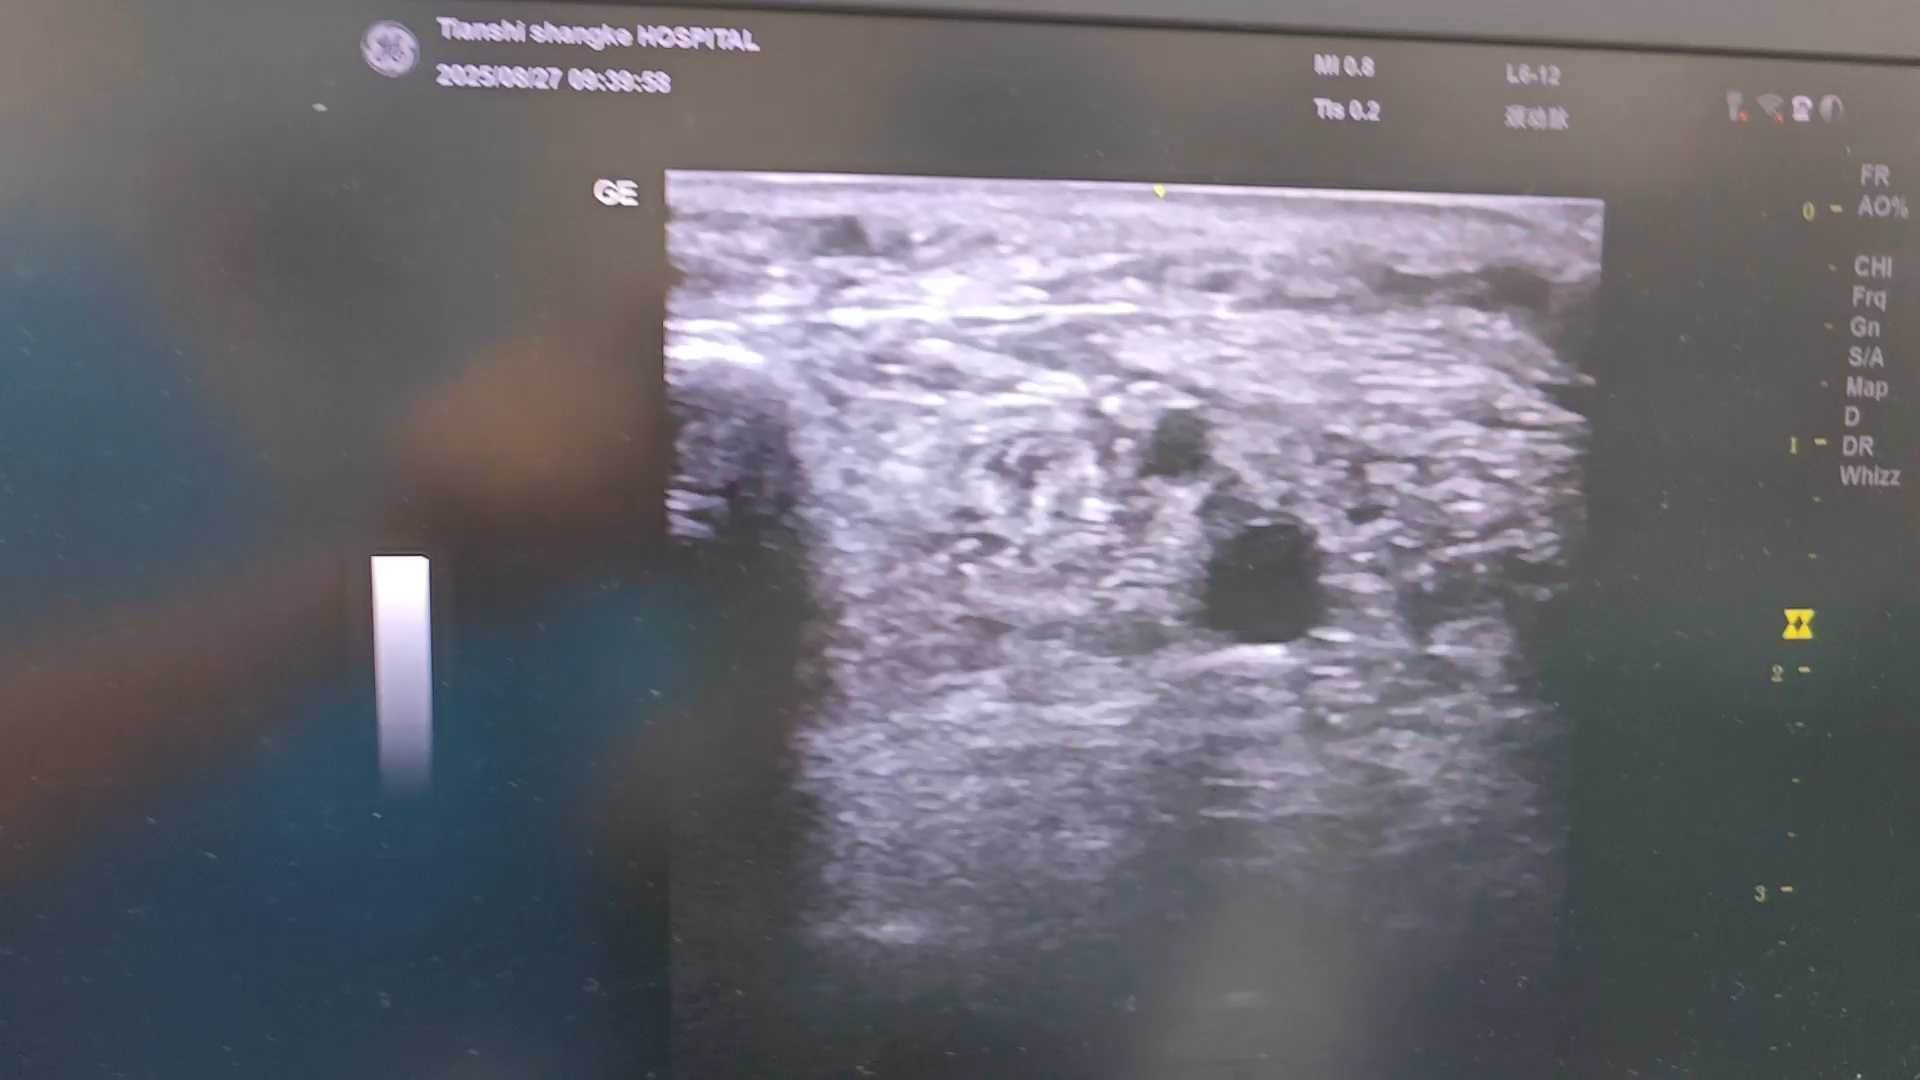

内踝评估探及明显增宽的病理性穿通静脉